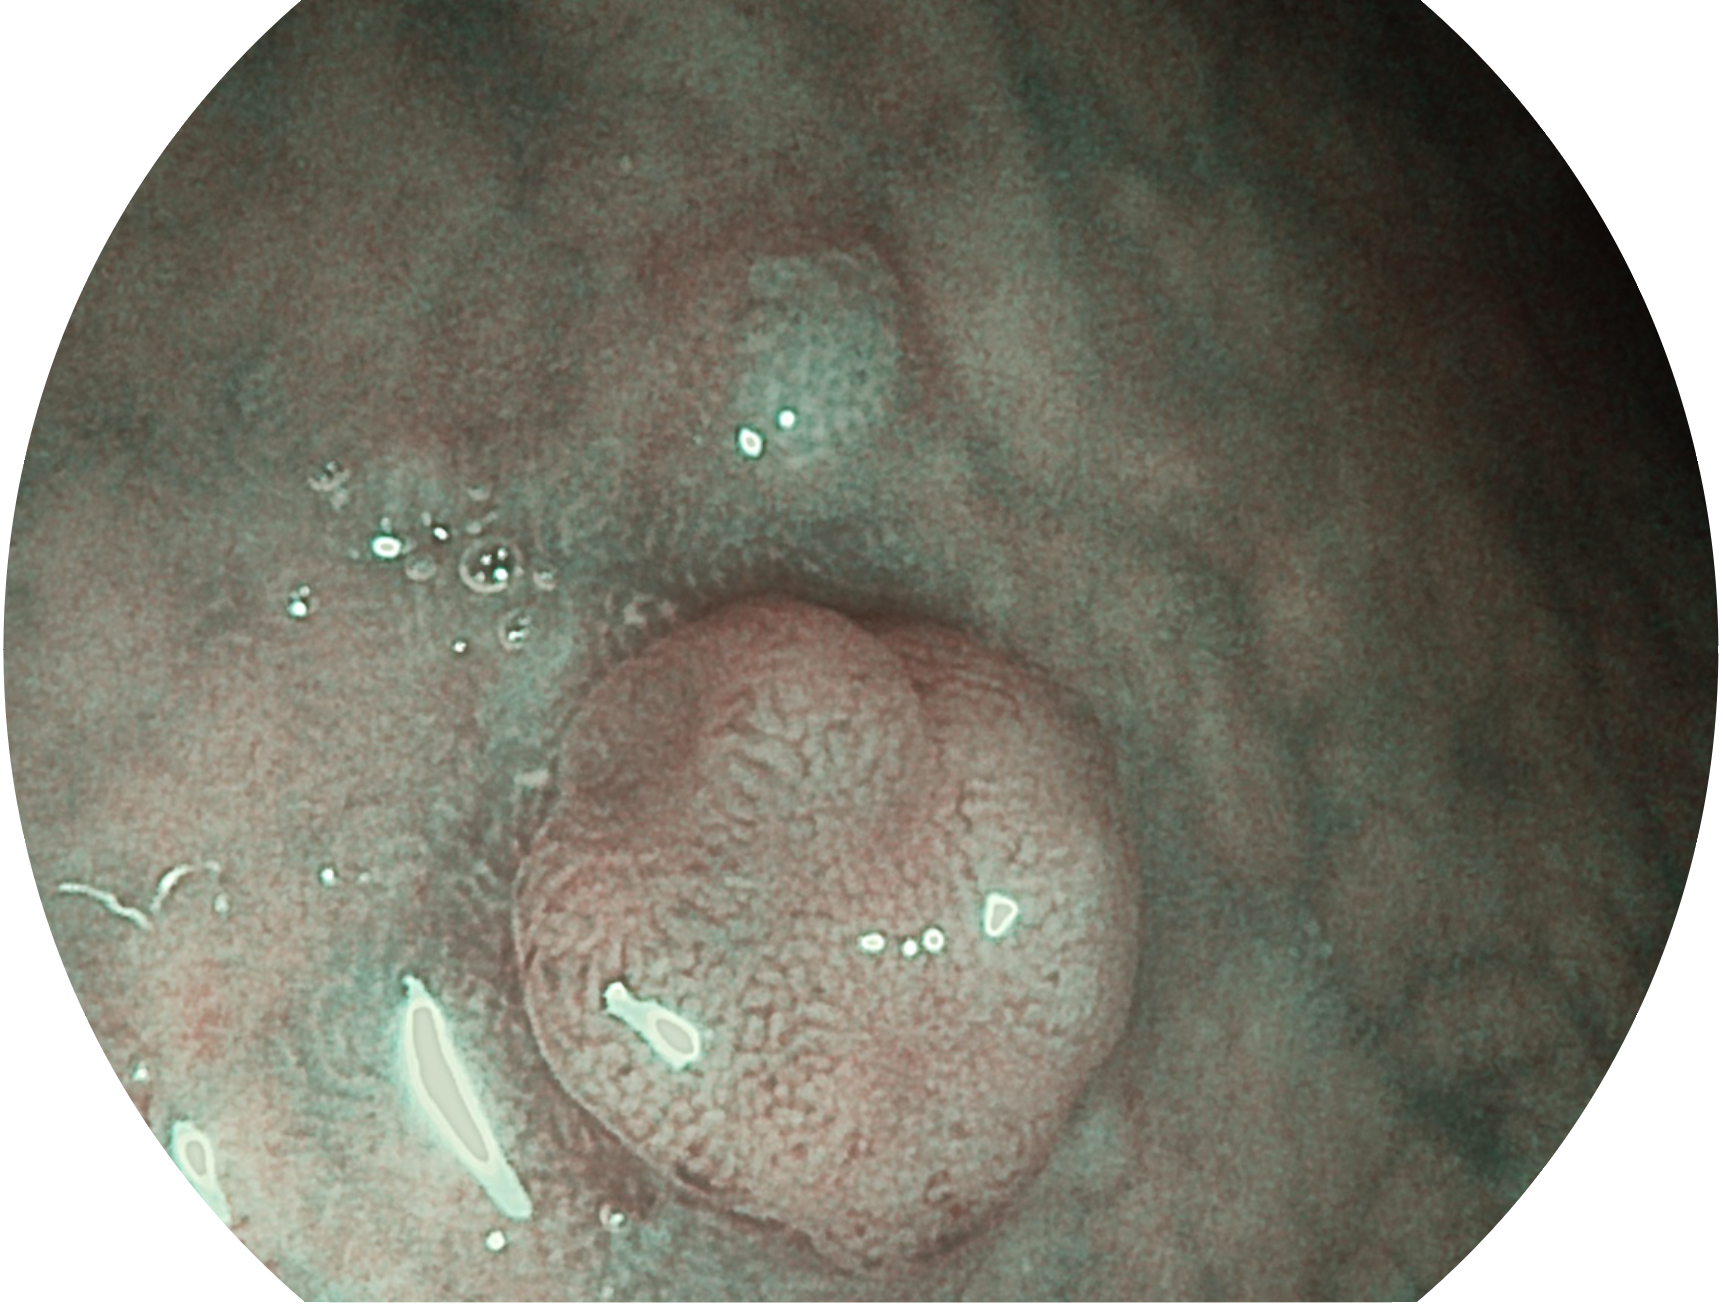

• 白光圖像 VIST圖像